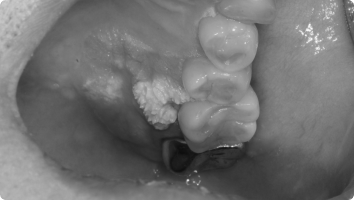

입안에도 혹처럼 불필요한 덩어리(종양)가 생길 수 있습니다.

그 중 흔히 볼 수 있는 것이 섬유종과 유두종입니다.

- 섬유종 : 잇몸, 뺨 안쪽, 혀 등에 자주 생기며, 오래된 자극(씹힘, 틀니, 교정 장치 등) 때문에 발생하는 경우가 많습니다.

- 유두종, 사마귀종 : 바이러스 감염이나 잦은 자극으로 인해 작은 사마귀처럼 돌출되는 양상을 보입니다.

대부분 양성(암 아님) 이지만, 크기가 커지거나 불편하면 제거하는 것이 좋습니다.

- 국소마취 후 병소 부위를 작게 절개하여 종양만 제거합니다.

- 필요한 경우 조직검사를 통해 정확한 진단을 확인합니다.

- 수술은 짧고 안전하게 진행되며, 회복도 빠릅니다.